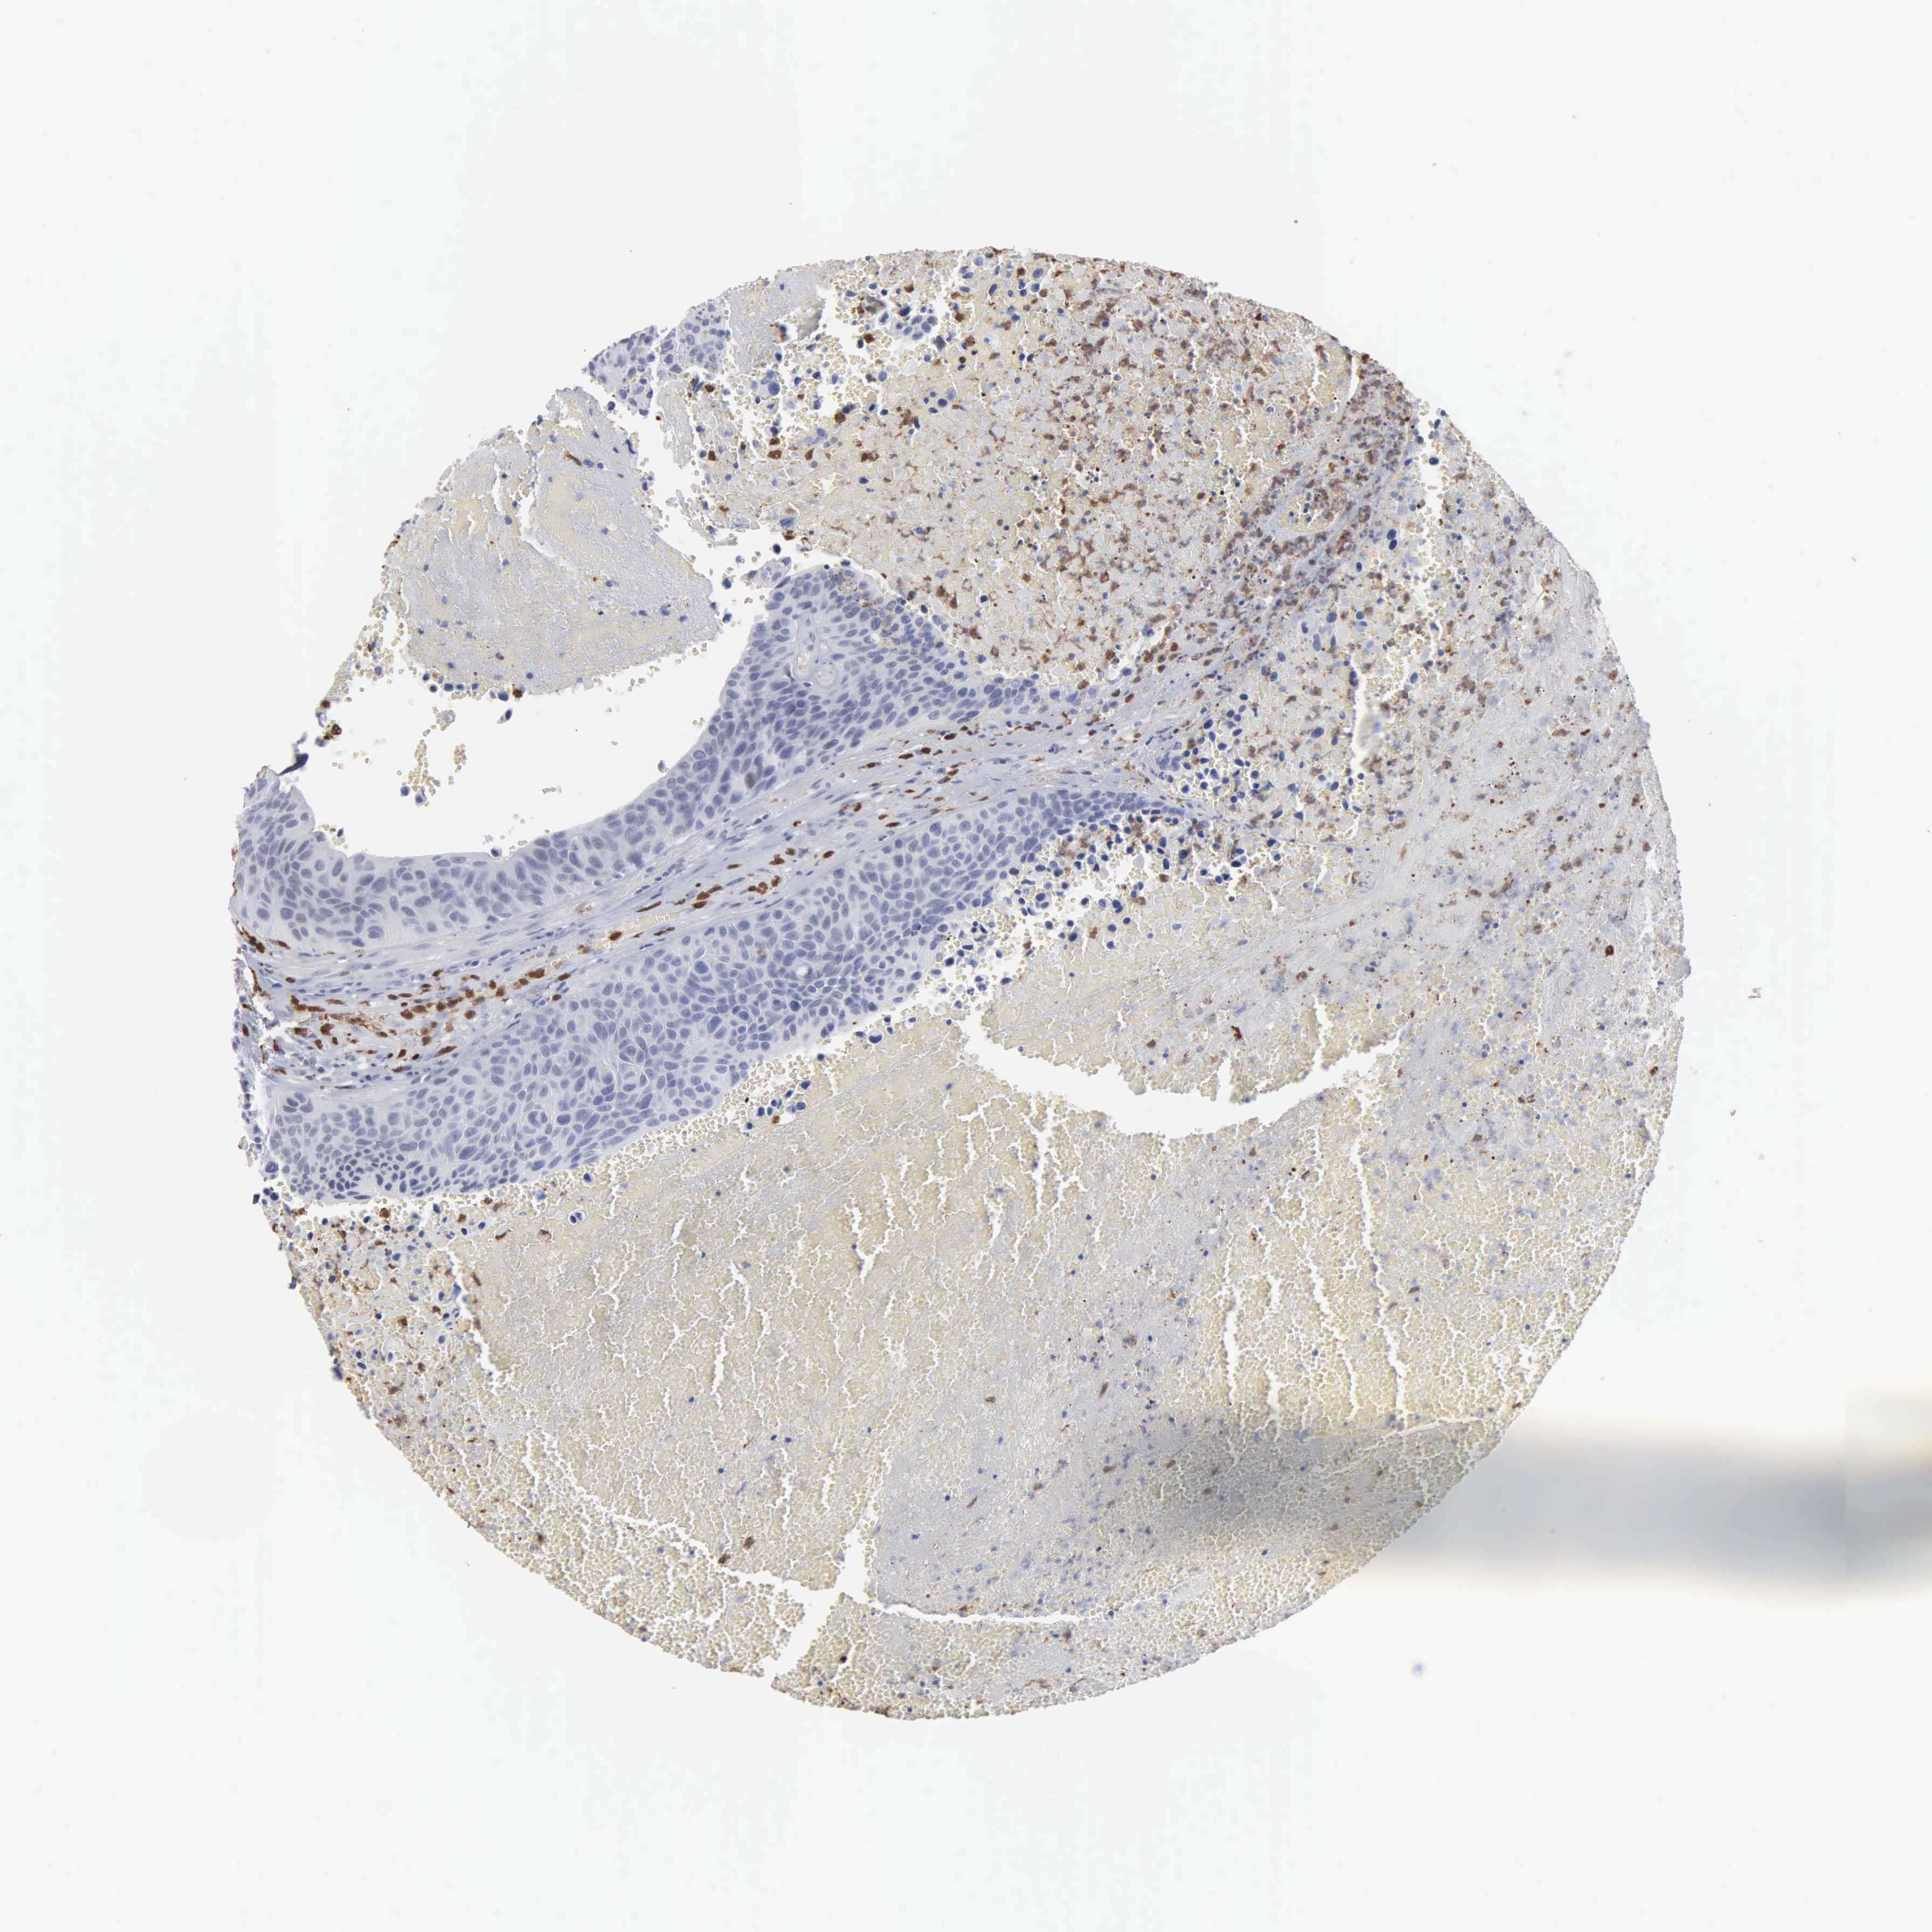

UROTHELIAL CANCER - Protein expressioni

A mouse-over function shows sample information and annotation data. Click on an image to view it in a full screen mode. Samples can be filtered based on level of antibody staining by selecting one or several of the following categories: high, medium, low and not detected. The assay and annotation is described here.

Note that samples used for immunohistochemistry by the Human Protein Atlas do not correspond to samples in the TCGA dataset.

Antibody stainingi

Antibody staining in the annotated cell types in the current human tissue is reported as not detected, low, medium, or high, based on conventional immunohistochemistry profiling in selected tissues. This score is based on the combination of the staining intensity and fraction of stained cells.

Each image is clickable and will lead to virtual microscopy that enables deeper exploration of all samples and also displays staining intensity scores, fraction scores and subcellular localization as well as patient and tissue information for each sample.

Antibody HPA000727

Staining

High

Medium

Low

Not detected

Intensity

Strong

Moderate

Weak

Negative

Quantity

>75%

75%-25%

<25%

None

Location

Nuclear

Cytoplasmic/membranous

Cytoplasmic/membranous,nuclear

Urothelial carcinoma, High grade

Urothelial carcinoma, Low grade